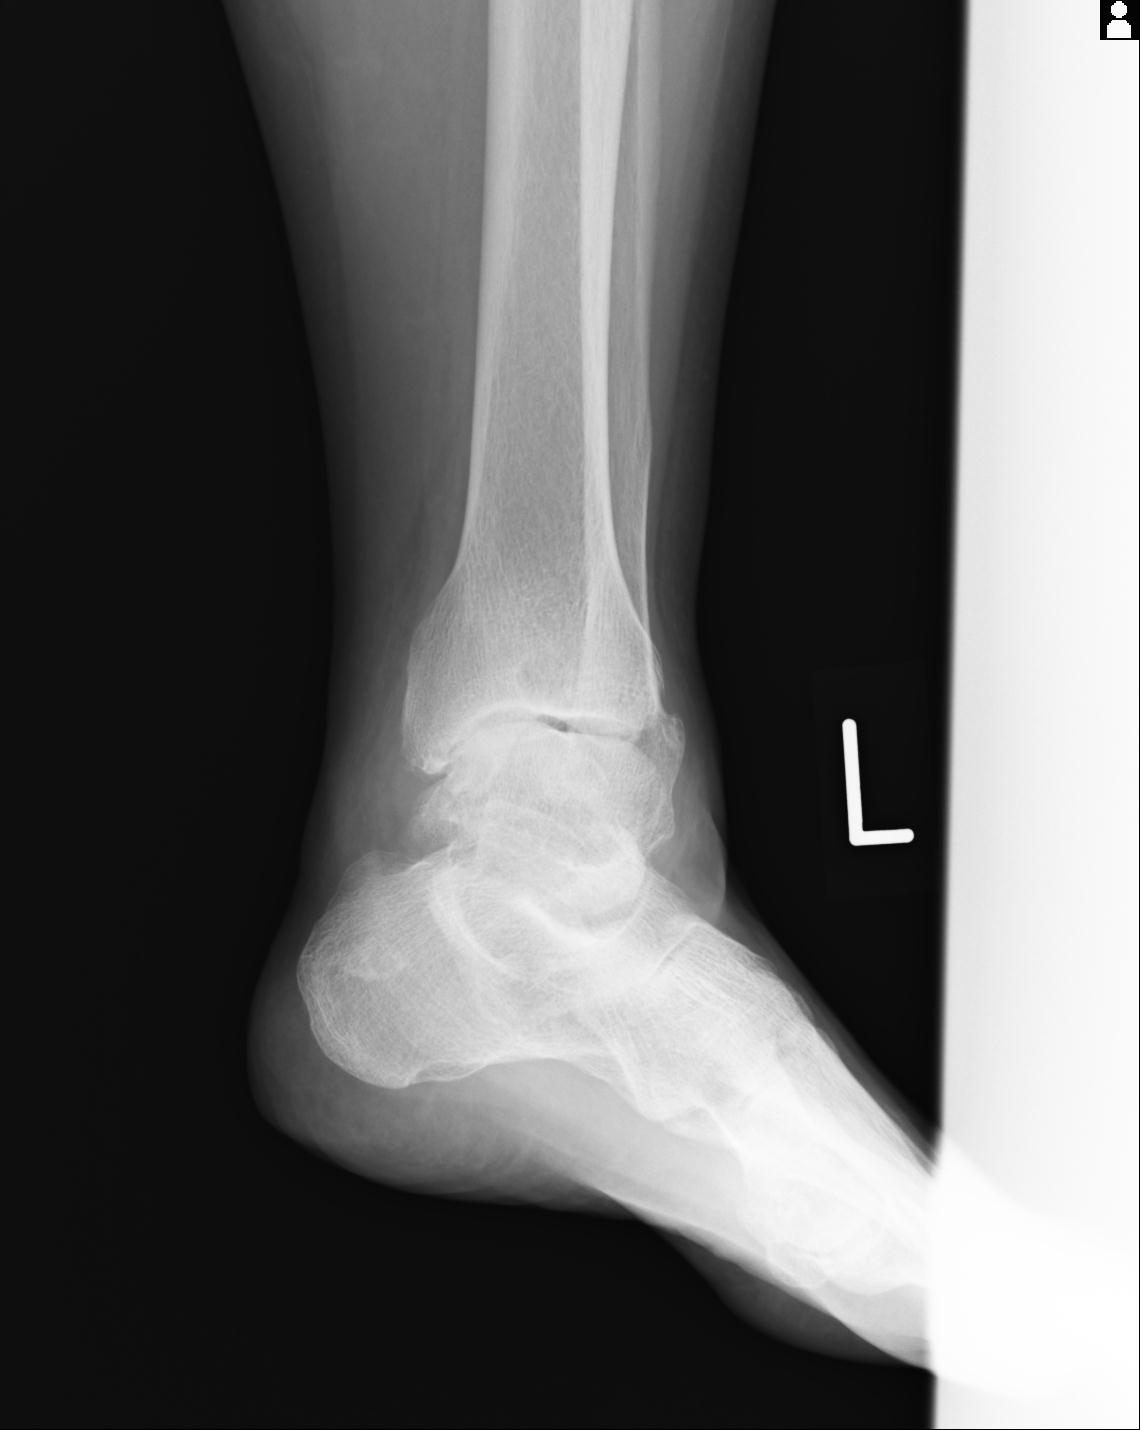

102755 1/4 2R 1/15 2R 右足関節 68歳女性 右三果脱臼骨折